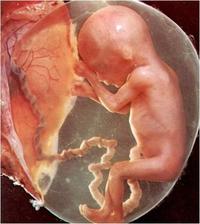

23.5. pro průkazku + odběr krve + utz 11+0 mimisek 4,2cm